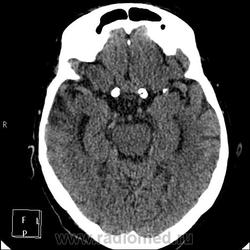

А контраст почему не делали? Больше похоже на тромбированные аневризмы

Неужели такие аневризмы? Бывает же! А сканы с контрастом есть?

Да простят моё нахальство уважаемые специалисты КТ. Я вижу тут огромные инкапсулированные узлы расположенные почти симметрично справа и слева от турецкого седла, которое разрушено узлом поменьше. Латеральные злы продавливают дно средней черепной ямы. По-видимому, здесь доброкачественная опухоль типа «аденома», исходящая из гипофиза и давно растущая. Обызвествление есть не только в капсулах узлов, но и в их толще (очаговое). При таких размерах узлов и косных разрушениях, нет сомнения, пострадали и зрительные нервы.

Цифровых и плёночных доказательств на руках нет. Опухоль диагностирована в 2004 году, размером "с вишню", дебютировала птозом века правого глаза, умеренной головной болью в лобной области слева и постепенным снижением зрения, катаракта. Пациентка с трезвом уме и превосходной памяти (на мой субъективный взгляд))). В выписке результаты КТ, МРТ: неоперабельная опухоль селлярно-параселлярной области с прорастанием кавернозных синусов, аневризма сифона внутренних сонных артерий. Цитологию НЕ брали.

Да, опухоль, в толще которой аневризма сифона ВСА. Причем с обеих сторон.

И то, и другое. Доказать без контрастирования не могу. Когда сама впервые увидела, анамнеза не знала, подумала о двусторонней аневризме. И не угадала.

Насчет опухоли у меня большие сомнения. То что седло растянуто, еще не показатель. Седло увеличивается в размерах даже при гипертонии,а тут такие аневризмы. Самой опухоли не видно, в просвете турецкого седла медиальные полюса аневризм. Ну впрочем не так это важно, интерес чисто теоретический, да и верификации видимо не будет. Спасибо большое за демонстрацию.